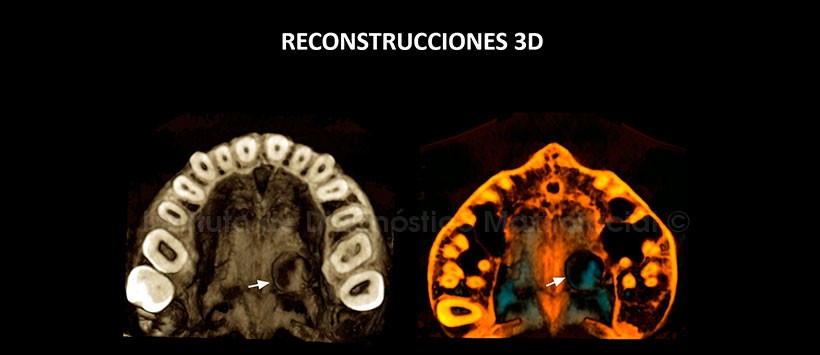

En las reconstrucciones 3D (Figuras 4 y 5) se aprecia la lesión antes descritas.